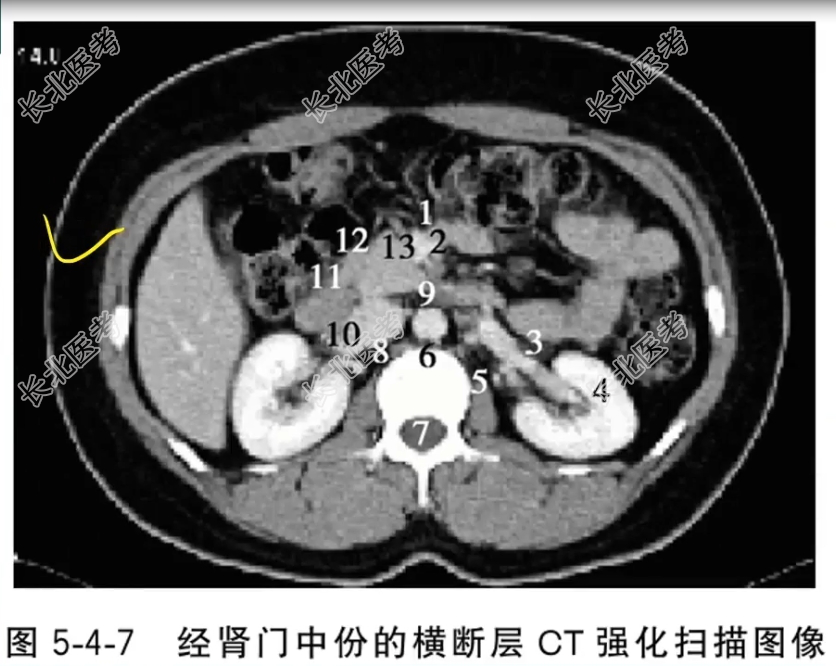

- 单项选择题经肾门中份的横断层CT强化扫描图像中,标记为3的结构是

A、肠系膜上静脉

B、肠系膜上动脉

C、左肾静脉

D、左肾

E、腰大肌